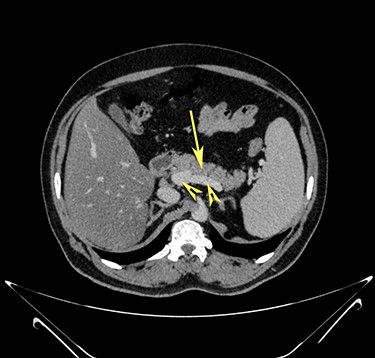

Transverse section image of a contrast-enhanced CT scan of the abdomen at level 1–1 (Fig. 1), showing the pancreas’ normal tail (long arrow). Splenic vessels are labelled using arrowheads.